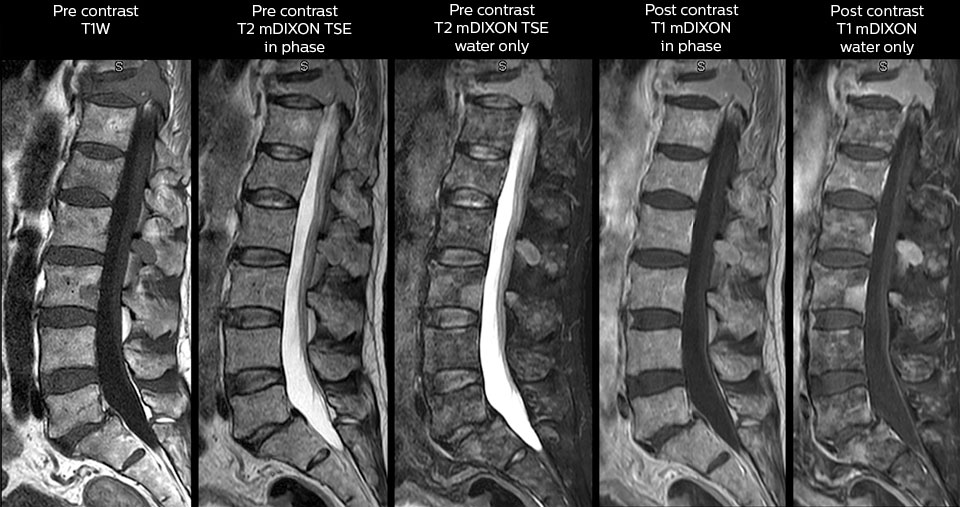

in image acquisition and postprocessing algorithms.”“mDIXON TSE sequences allow simultaneous characterization of morphological changes from the in-phase T2-weighted images and visualization of edematous changes, thanks to the water T2-weighted images from the same acquisition. Anatomical and morphological considerations could be a partial or complete ligament tear, a bony avulsion or hematoma.” “For soft tissue assessment mDIXON brings similar benefits. For example in one T2-weighted mDIXON TSE acquisition, having the multiple contrasts helps us assess abnormalities in peripheral nerves fascicles, which may be due to anatomical or inflammatory changes..” “In peripheral joints, we get good image quality in difficult areas with mDIXON TSE. Fat suppressed images appear homogeneous over the entire image, even with large coverage at 3.0T – for instance in scapular or hip girdles – or in the bearing areas or around metal prostheses*, where fat suppression is often deficient with STIR or spectral fat suppression, causing diagnostic difficulties. If a diagnostic image is right the first time, we don’t need to repeat or add a sequence.” “mDIXON TSE sequences allow simultaneous characterization of morphological changes from the in-phase T2-weighted images and visualization of edematous changes, thanks to the water T2-weighted images from the same acquisition. Anatomical and morphological considerations could be a partial or complete ligament tear, a bony avulsion or hematoma.” “For soft tissue assessment mDIXON brings similar benefits. For example in one T2-weighted mDIXON TSE acquisition, having the multiple contrasts helps us assess abnormalities in peripheral nerves fascicles, which may be due to anatomical or inflammatory changes..”

To minimize the time taken to perform scans, rapid MRI examination protocols (ExamCards) were developed, shortening the total scanning time to even less than 10 minutes in some exams. Techniques like mDIXON (modified DIXON) are used for robust capturing of fat-free MRI images in a hectic ED environment.

“We use mDIXON TSE extensively in our spine imaging in the emergency room,” says Dr. Karis. “It’s particularly nice in that it is very robust with regard to susceptibility type of problems that would come up with traditional spectral fat-saturated images; these problems are essentially eliminated with the mDIXON technique. In our ED environment it’s really nice to have the fat-free imaging that goes along with the mDIXON technique.